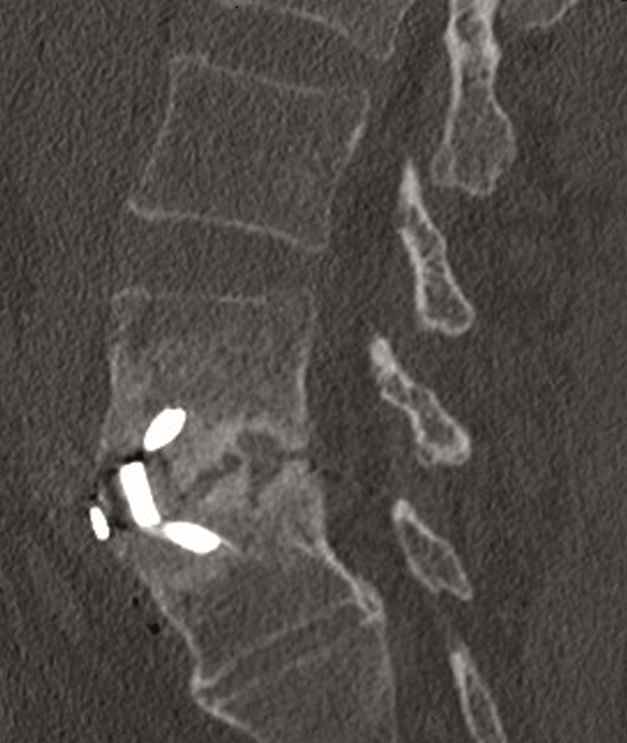

A 40-year-old man 5 years after ALIF L4-L5 using SynFix with axial low back pain. The CT scan shows locked pseudarthrosis (Fig 17). Nonoperative treatment failed. The treatment option was bilateral Facet Wedge at L4-L5.

A less invasive approach was used with Insight Retractor using the bilateral Facet Wedge. No bone graft. X-ray follow-up after 3 months and CT assessment after 6 months (Fig 18-19).